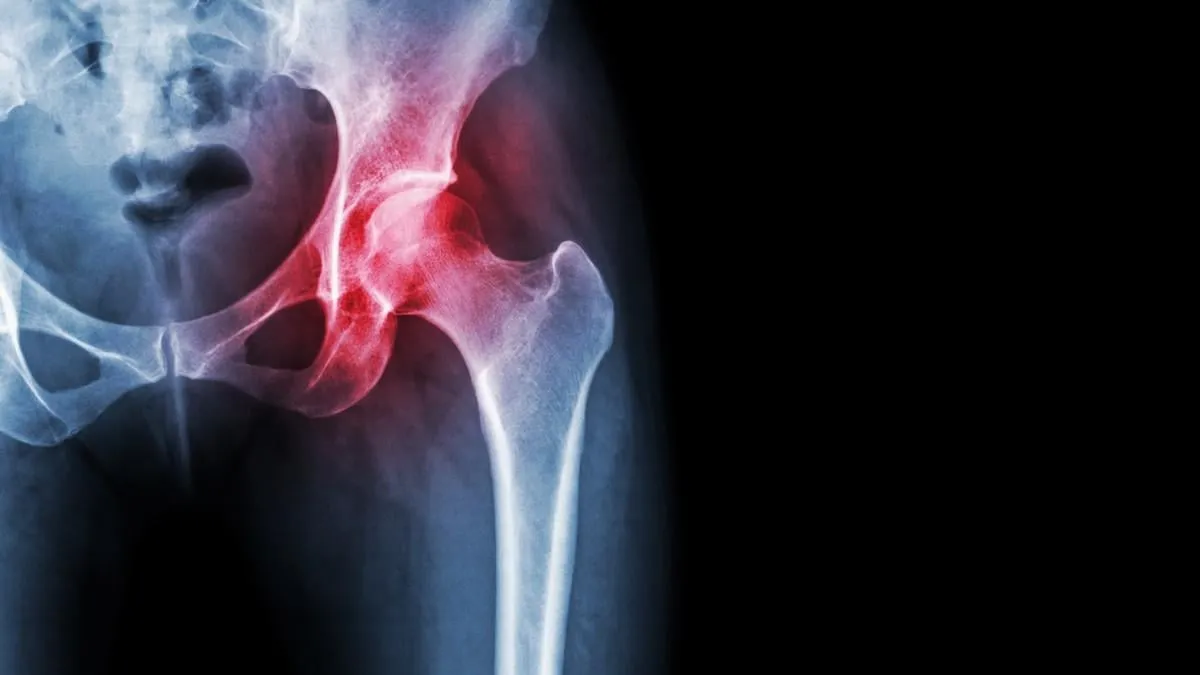

arthritis at hip joint film x-ray show inflamed of hip joint and blank area at right side avascular necrosis concept

Les raisons de la pose d’une prothèse de hanche

Une prothèse de hanche est une des opérations les plus courantes en France avec près de 150 000 personnes concernées. Elle permet de remplacer la partie malade de l’articulation de la hanche.

Il y a plusieurs raisons qui poussent des personnes à vouloir se faire poser une prothèse de hanche :

• Ceux qui ont de l’arthrose (dégénérescence du cartilage au niveau des articulations)

• Ceux qui ont une fracture de la hanche après une simple chute

• Ceux qui ont une déformation génétique de la hanche

• Ceux qui souffrent d’ostéoporose (vieillissement des os)

A noter : Elles ont toutes un point commun. Pour le docteur Benoit de Courtivron, chirurgien orthopédique, "elles souhaitent cette opération car la souffrance est trop importante. Le handicap est devenu très douloureux et les médicaments ne suffisent plus à les soulager".